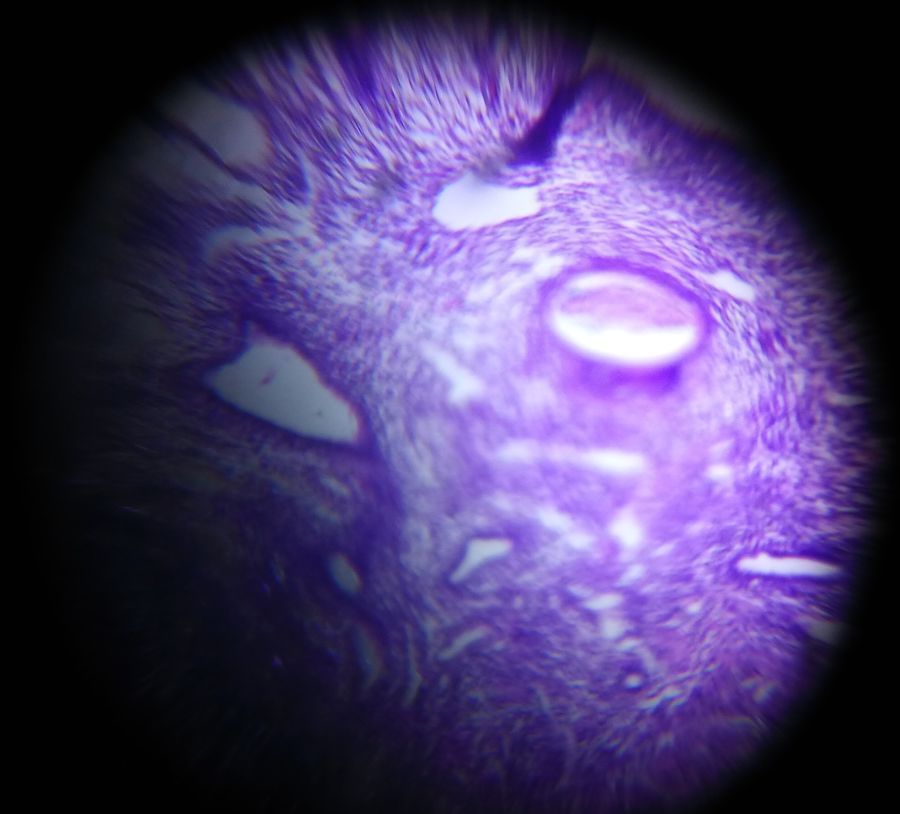

Secreatory Endometrium

Applause Icon140x Magnification

Secreatory Endometrium showing dilated endometrial glands filled with secreation seen under Foldscope by the student of R D Gardi Medical College, Ujjain